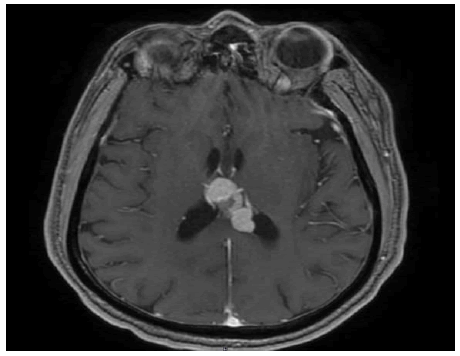

In June 2016, a 57-year-old gentleman presented to the internal medicine department with complaints of recurrent episodes of low-grade fever, headache, and lethargy for about three months. He had already undergone multiple hospital admissions for the same during this period and had been extensively tested. Other than undergoing atrial septal defect closure in December 2015, the patient (who has been on oral aspirin since then) has no other significant medical history or comorbidities. On general evaluation, he was found to have a well-built and nourished physique and was well-aware and oriented. He was febrile (temp: 100.10°F) and pallid. Furthermore, routine blood investigations showed evidence of anaemia and thrombocytopenia. Blood and urine cultures showed no significant growth. The workup for the infectious panel, including leptospirosis, dengue, malaria, and tuberculosis, was reported negative. The autoimmune workup Antinuclear Antibody (ANA) profile, antineutrophil cytoplasmic antibodies (c-ANCA, and p-ANCA) was also found to be negative. An Ultra Sonogram (USG) of the abdomen showed mild hepatosplenomegaly and enlarged bilateral adrenals. Further, a 2D echocardiography (2D ECHO) and transesophageal ECHO showed a normal study besides the previous ASD closure changes; hence, infective endocarditis was ruled out. A bone marrow aspiration and biopsy indicated hypercellular marrow with erythroid preponderance. Provisionally, it was diagnosed as probable macrophage activation syndrome and was therefore treated with steroids. The patient’s condition improved subsequently, and he was discharged afterwards; two weeks later, however, he was readmitted with altered sensorium and lethargy. Since his condition was found to be gradually deteriorating, a whole-body PET-CT was done, which showed significantly enlarged bilateral adrenal glands (Figure 1). He underwent an adrenal biopsy, which showed a neoplasm composed of cells predominantly seen in the intravascular compartment. The cells were large with moderate eosinophilia cytoplasm, round to ovoid nuclei with coarse chromatin and scattered mitosis (Figure 2a). An Immunohistochemistry (IHC) lymphoma panel was done, and the neoplastic were found to be positive for LCA, CD20 (Figure 2b), PAX-5, BCL2, and MUM-1 and negative for CK, CD3, BCL6, CD10, and TdT. Moreover, the Ki67 index was 60% focally. The neoplastic cells seen within vascular channels were highlighted by the endothelial marker, CD34 (Figure 2c), and based on these findings a diagnosis of intravascular large B cell lymphoma was made.

Figure 1: Enlarged adrenal glands in PET CT